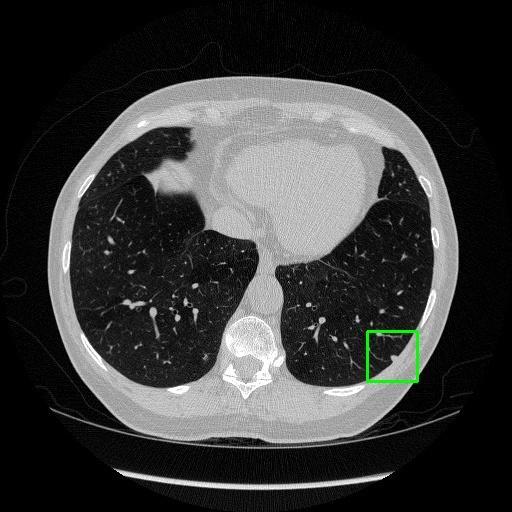

We developed an AI-based system using deep learning models for analyzing lung CT scans to detect and classify pulmonary nodules. We chose the YOLOv11 architecture for its enhanced object detection capability and adapted it specifically for medical imaging, incorporating pixel-level precision and severity classification.

Classification into three severity levels with colored bounding boxes.

Successfully built and deployed an AI model (YOLOv11) capable of detecting lung nodules in CT scans with high accuracy and real-time performance.

Designed a severity classification system that categorizes nodules into null, moderate, and severe using colored bounding boxes, assisting in rapid clinical decision-making.